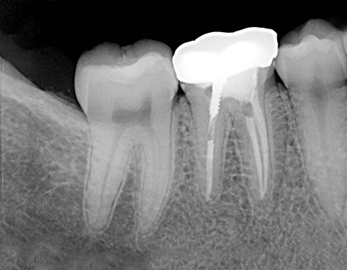

Retroalveolarni snimak / Retrokoronarni snimak

Retroalveolarni snimak, dentalni radiogram, mali snimak zuba, dentalni snimak pojedinačnih zuba na kome se u zavisnosti od situacije u ustima pacijenta može videti najviše tri zuba. Stomatolog koristi ovaj snimak da bi video patološke promene na odredjenom zubu ili kao kontrolni snimak u toku ili po završetku lečenja zuba.